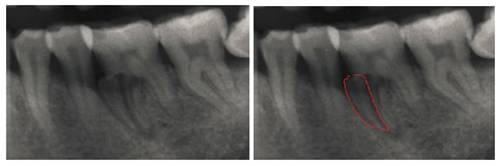

再来一个牙根劈裂的